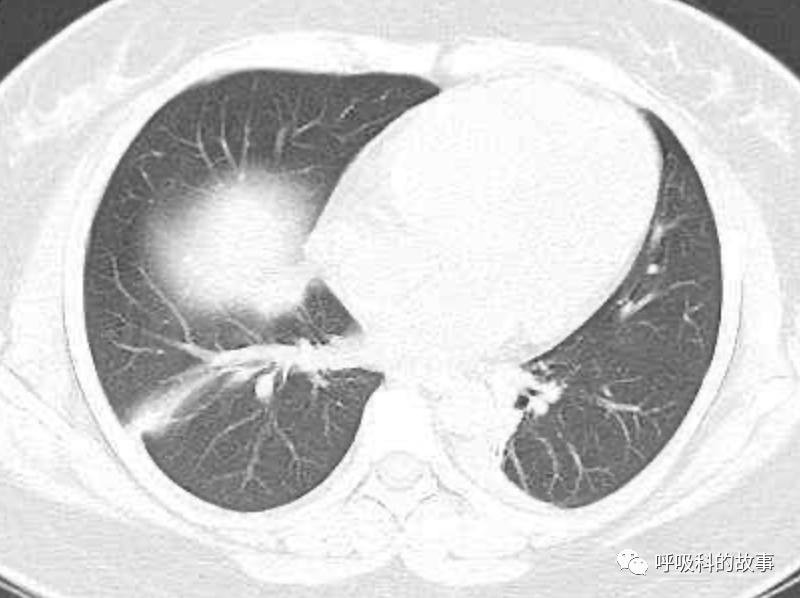

患者发热后行胸部CT检查(6月21日,住院第13天),可见两下肺有条片影,当时考虑是肺炎引起的发热。

可是在6月26日(往院第18天)仍持续发热的情况下复查肺部CT,肺部病灶已明显吸收了。那么患者发热的原因到底是什么呢?为什么患者高热的情况下血白细胞不升反降,C反应蛋白也没有明显增高?这个时候消化科医生也迷茫了,这可怎么办?于是请感染科和呼吸科医生一起会诊,共商计策。